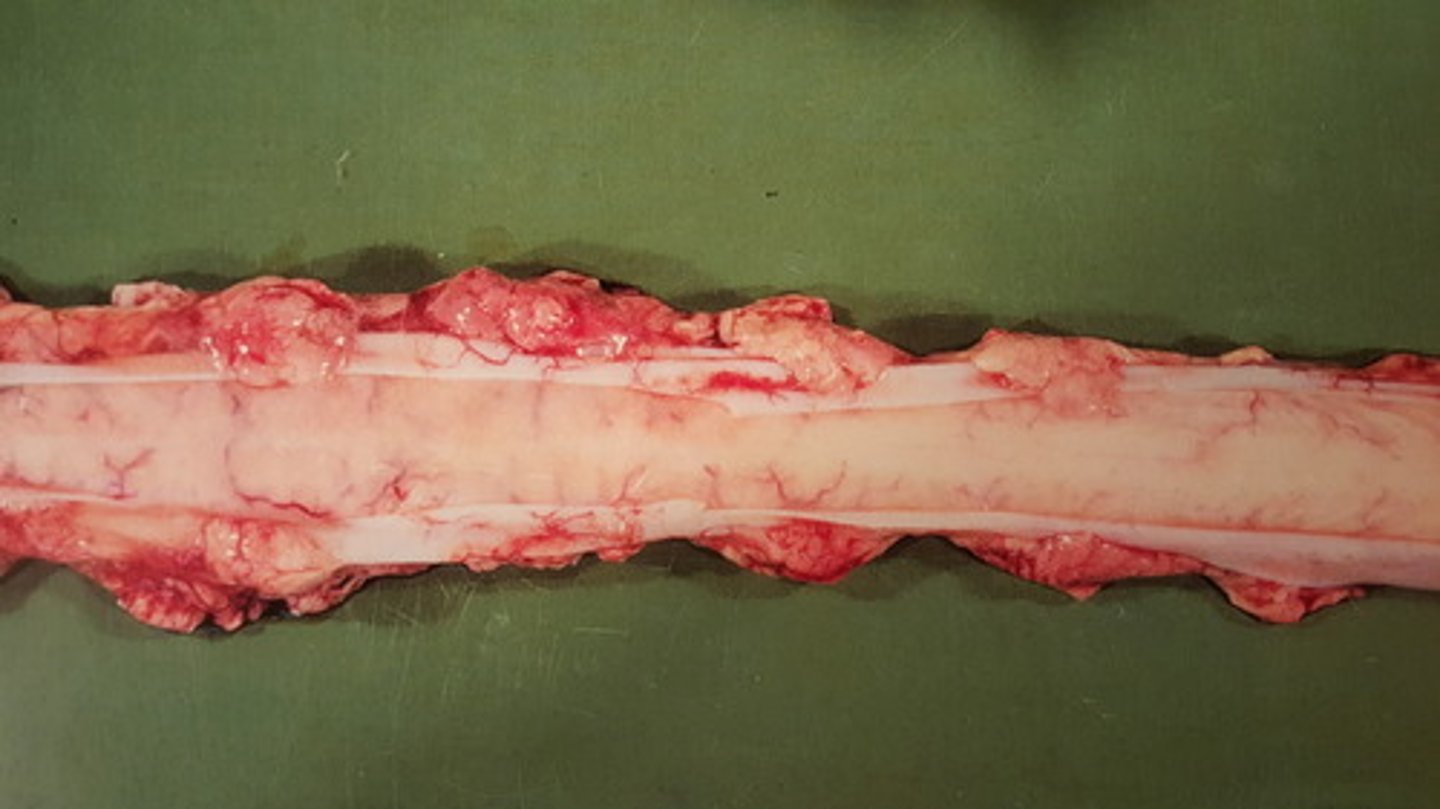

multicentrisk schwannom

Canalis vertebralis - okse. Patoanatomisk diagnose?

udbredt forekomst af Schwannomer

Perifere nervesystem hos okse. Patoanatomisk diagnose?

multiple Schwannomer

Intercostalnerver hos okse. Patoanatomisk diagnose?

R=ribben, N=nerver, I=muskulatur